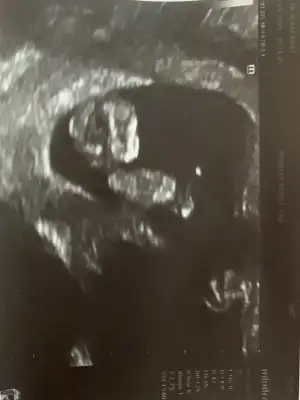

Merhaba arkadaşımın bebeği için cinsiyet yorumlarmısınız ☺️☺️

Eklentiler

• F17F74DB-0A55-4017-AE3F-ACD7B369930D.webp

F17F74DB-0A55-4017-AE3F-ACD7B369930D.webp

21,2 KB · Görüntüleme: 47